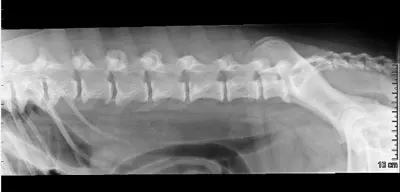

Lateral radiograph of a canine spine showing clear alignment of the vertebrae, with no signs of fractures or abnormalities. The surrounding soft tissue structures are also visible, providing context for the spinal anatomy.

Although bony proliferation of the facets is usually external to the vertebral canal, spinal stenosis leading to spinal cord compression is possible; however, more common conditions, such as disk herniation, should be ruled out in dogs with neurologic signs and spinal pain. Arthritis in the lumbosacral region can be associated with cauda equina syndrome.